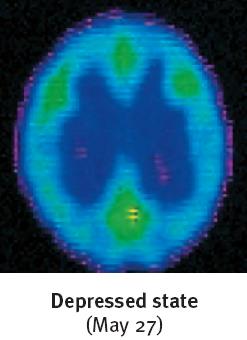

Biological Basis of Mood Disorders

Brain imaging studies show that brain activity is diminished in depression and increased in mania. Structural differences include smaller frontal lobes in depression and fewer axons in bipolar disorder. Neurotransmitter imbalances are also implicated: reduced serotonin in depression and increased norepinephrine in mania.